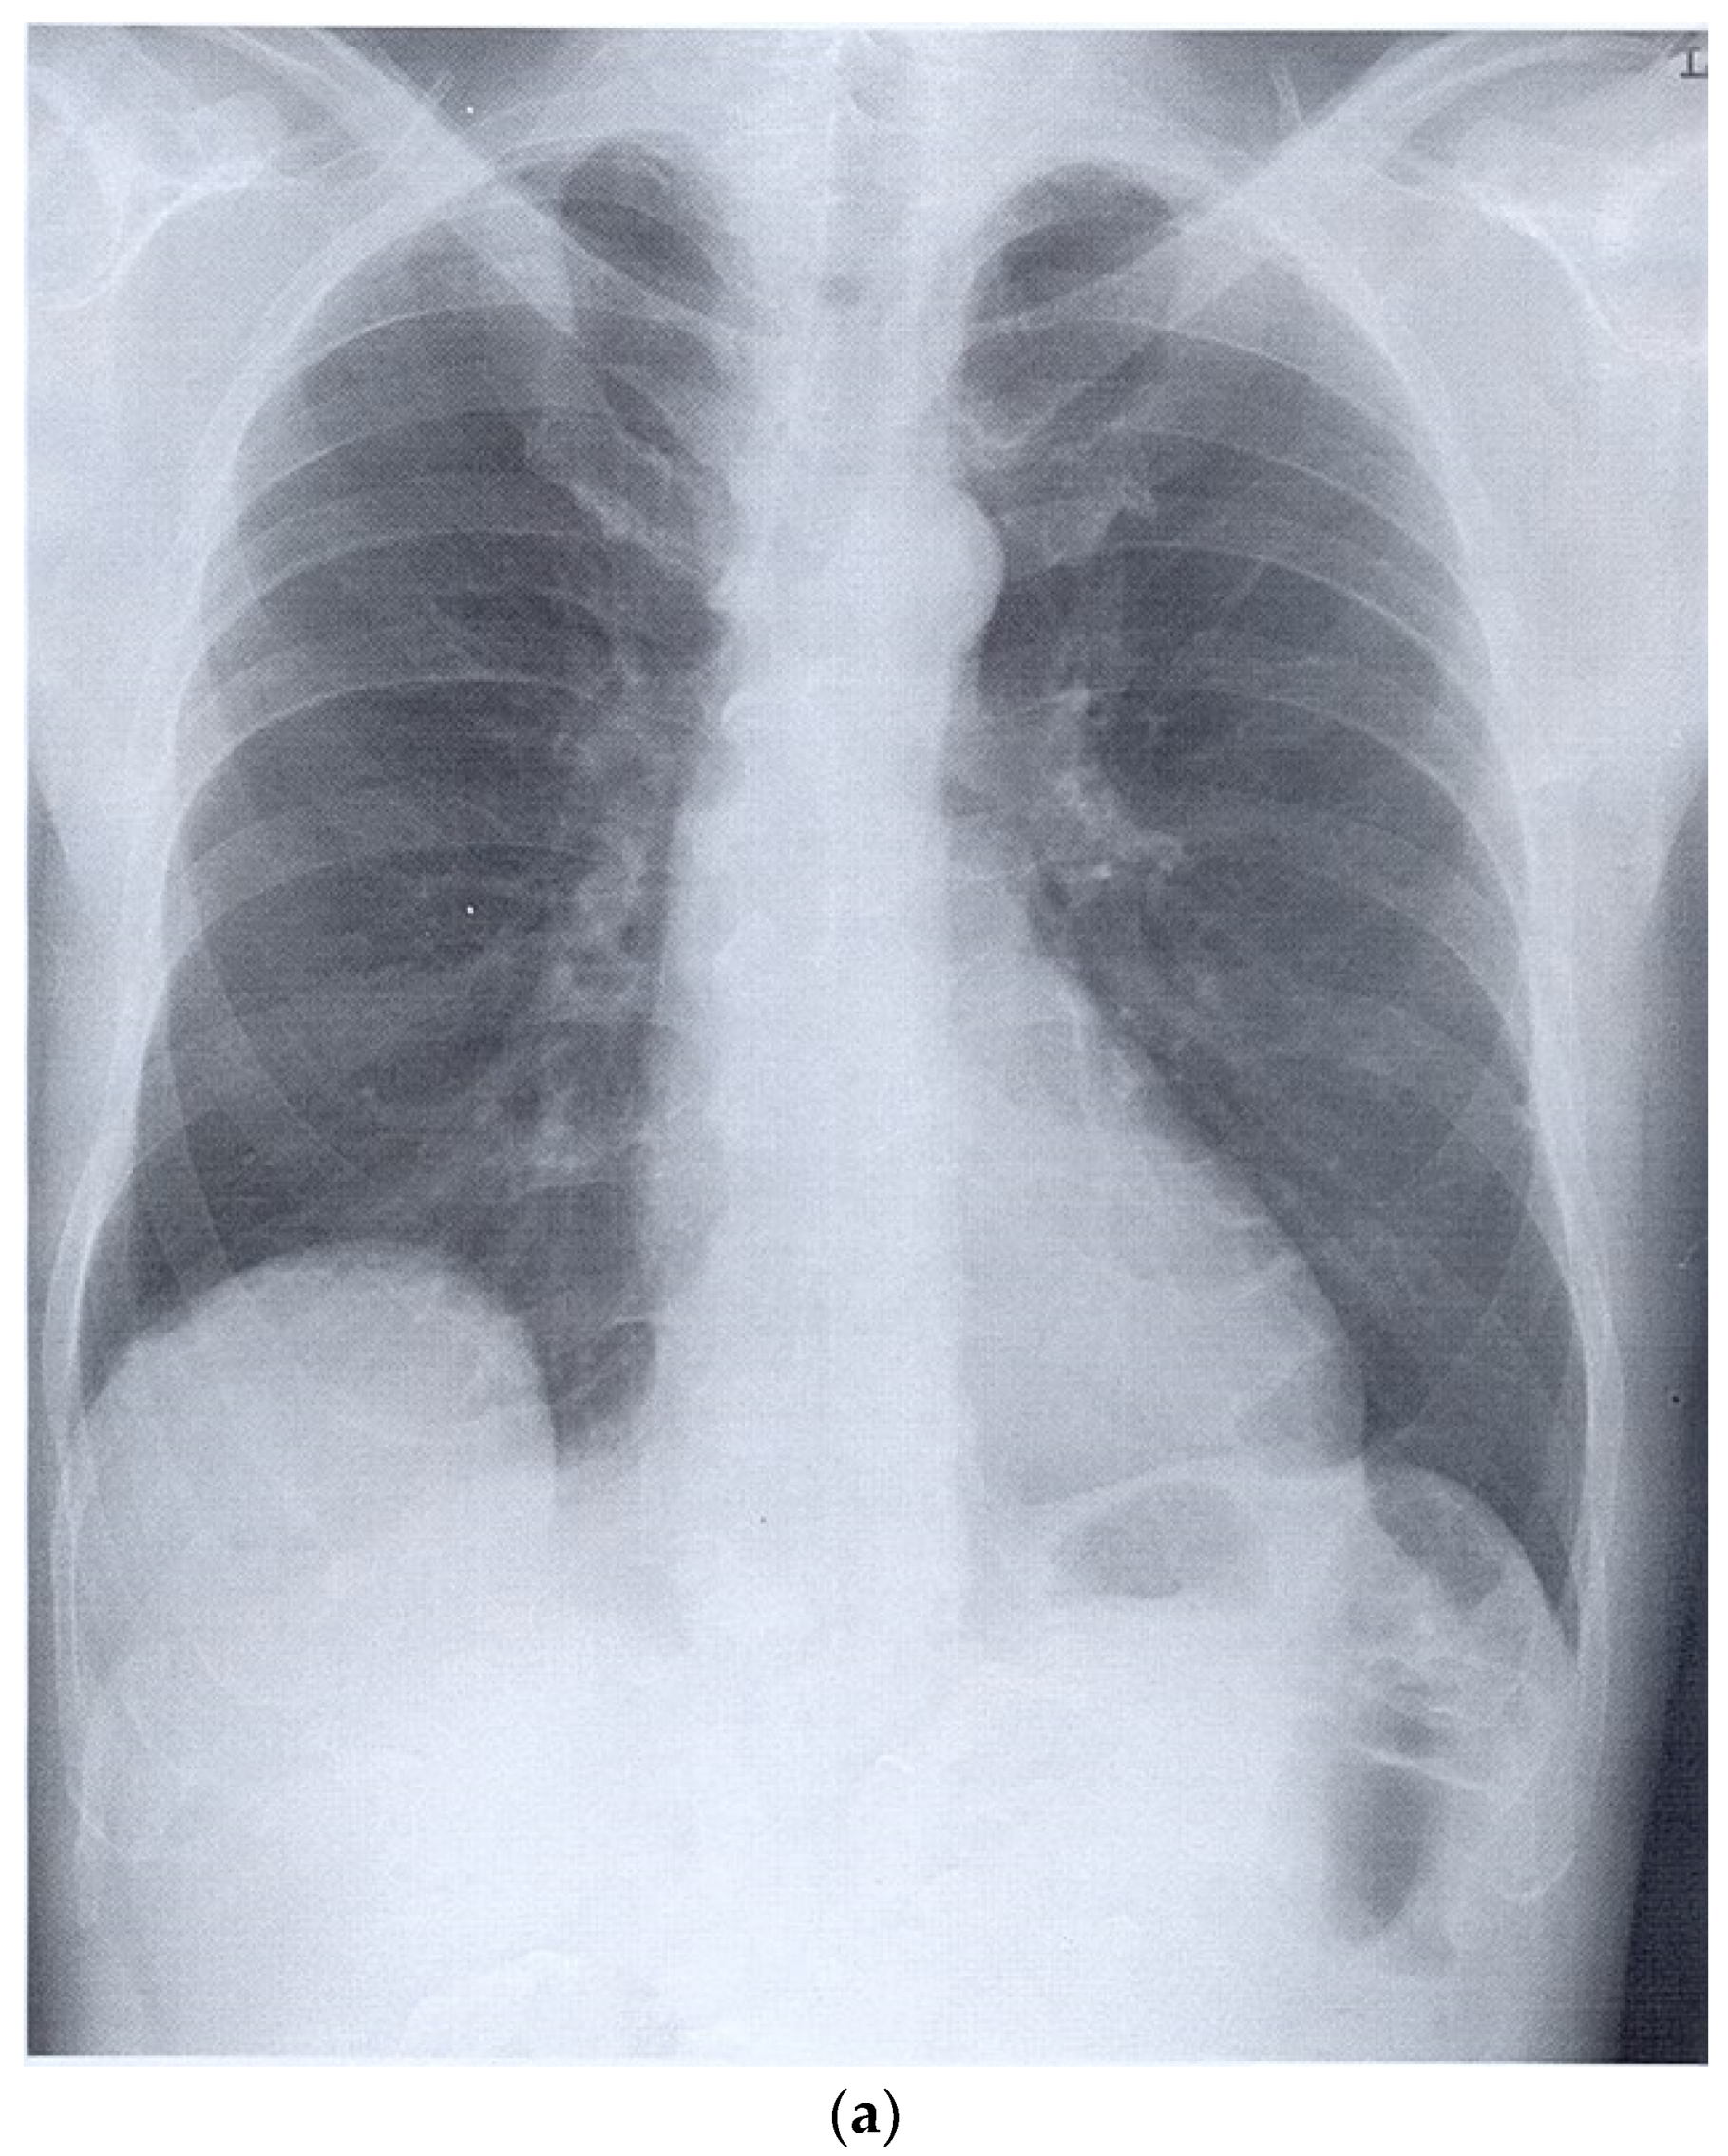

| Hemothorax | Pleural effusion, blood appears as hypoechoic content. Pleural thickening, fibrin, and septa may form. |